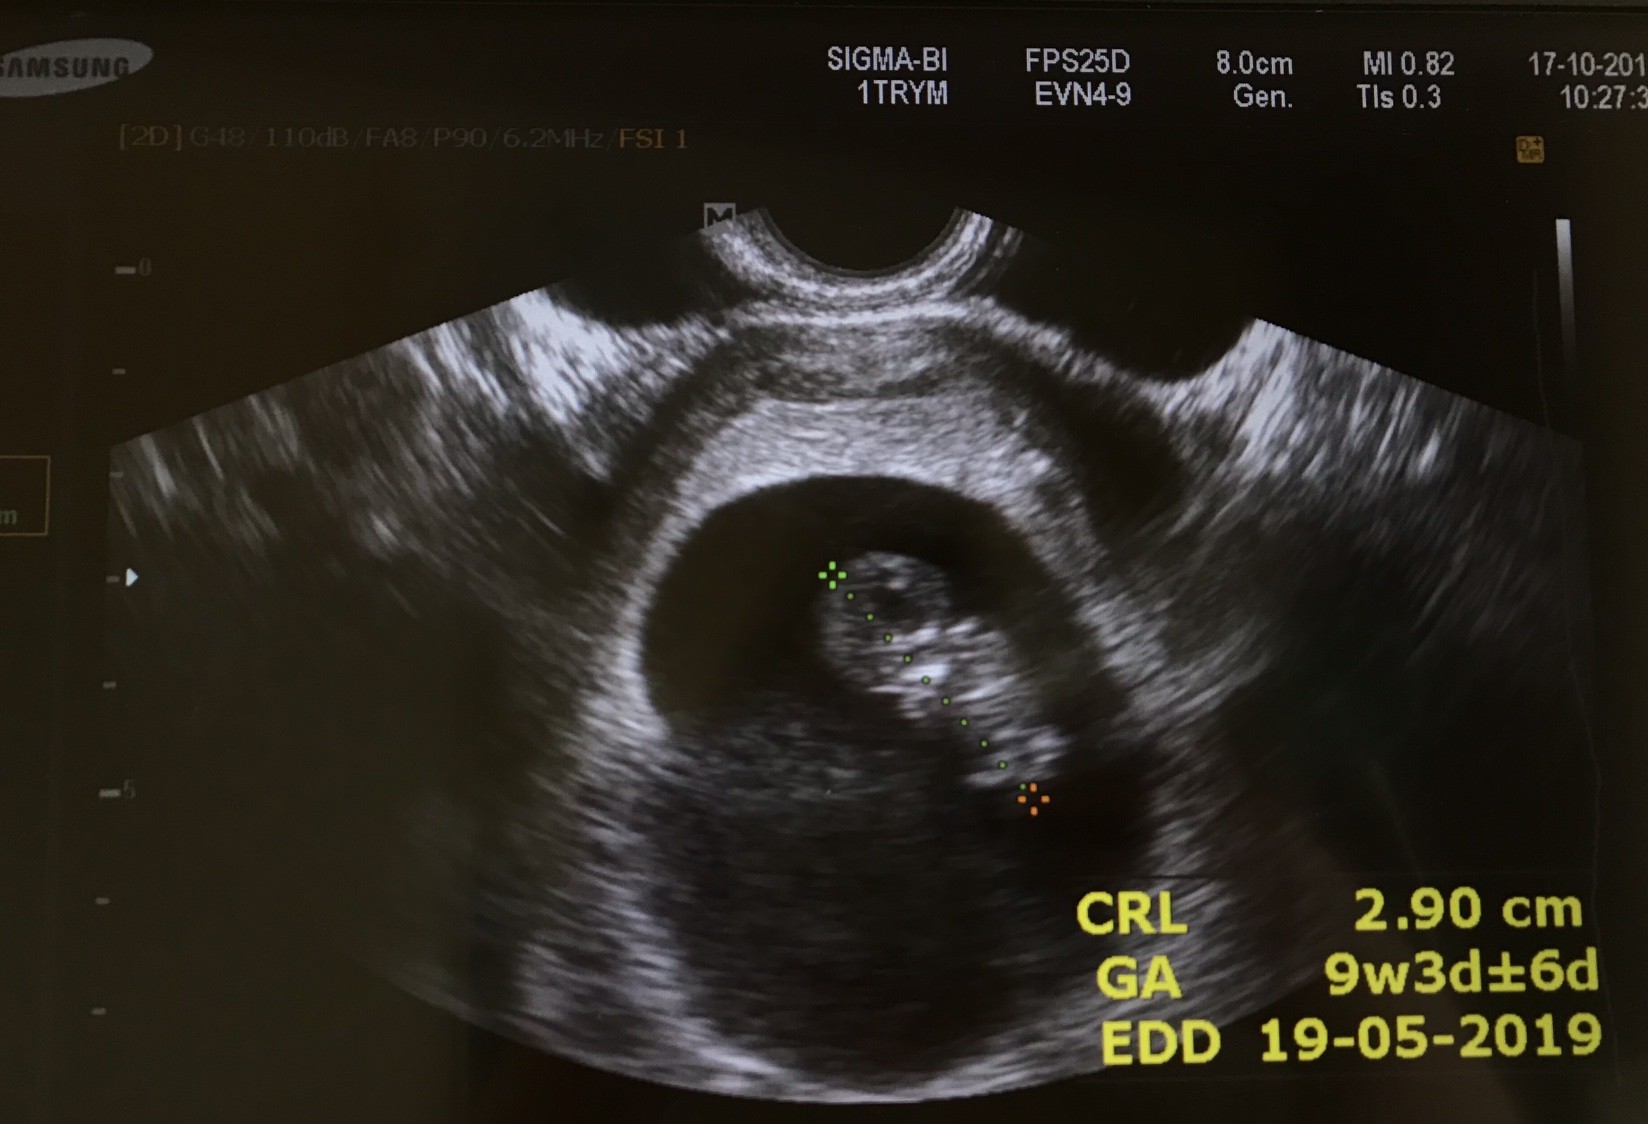

Widziałam pięknie bijące serduszko mojego robaczka, podrzucam wam zdjęcie z dzisiaj :)

Wszystko jest w porządku, wyniki także, dzidzia jest te dwa tygodnie młodsza, bo om miałam 30.07 i to powinien być 12 tydzień, a jest 10. W przychodni wielkie zamieszanie bo im się nie zgadza i nie umiały się doliczyć dwa tygodnie do przodu. Prenatalne mam 30.10, a kolejna wizyta u gin 7.11.